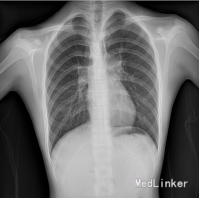

胸片:肺血少,肺无实变,双膈光整,心影无特殊